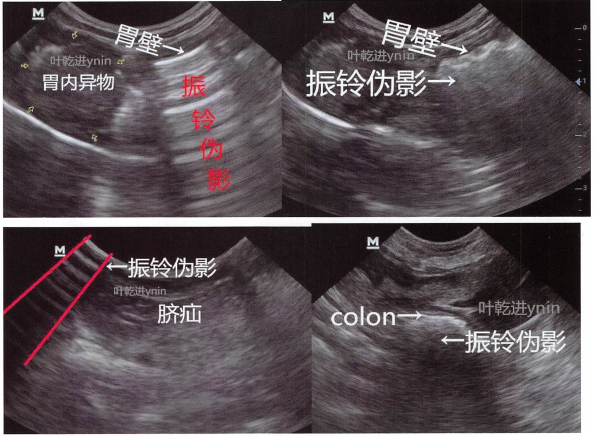

c.混响(又称振铃伪影):高声阻抗差异的界面,可产生多次反射,显示为声强降低的与源回声平行的多条线。如胃肠道,皮肤与探头之间的接触不良。

f,侧边声影:膀胱,卵巢,肠套叠,尿道等圆形结构的侧边出现声影。请翻看相关章节的图像。着重理解:圆形结构的侧边声波发生了特殊折射,产生声影。另外本书封面第3张图套叠肠管两边有侧边声影。